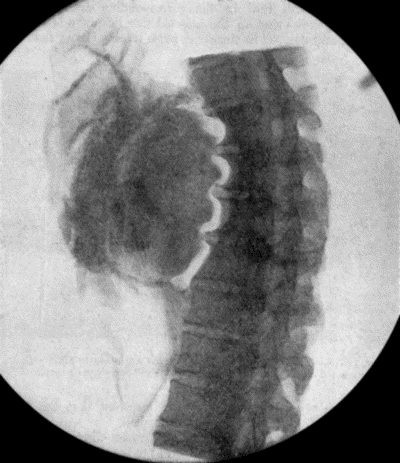

300 71.Radiogram of Aneurysm of Aorta

304 73.Radiogram of Innominate Aneurysm after Treatment by Moore-Corradi method